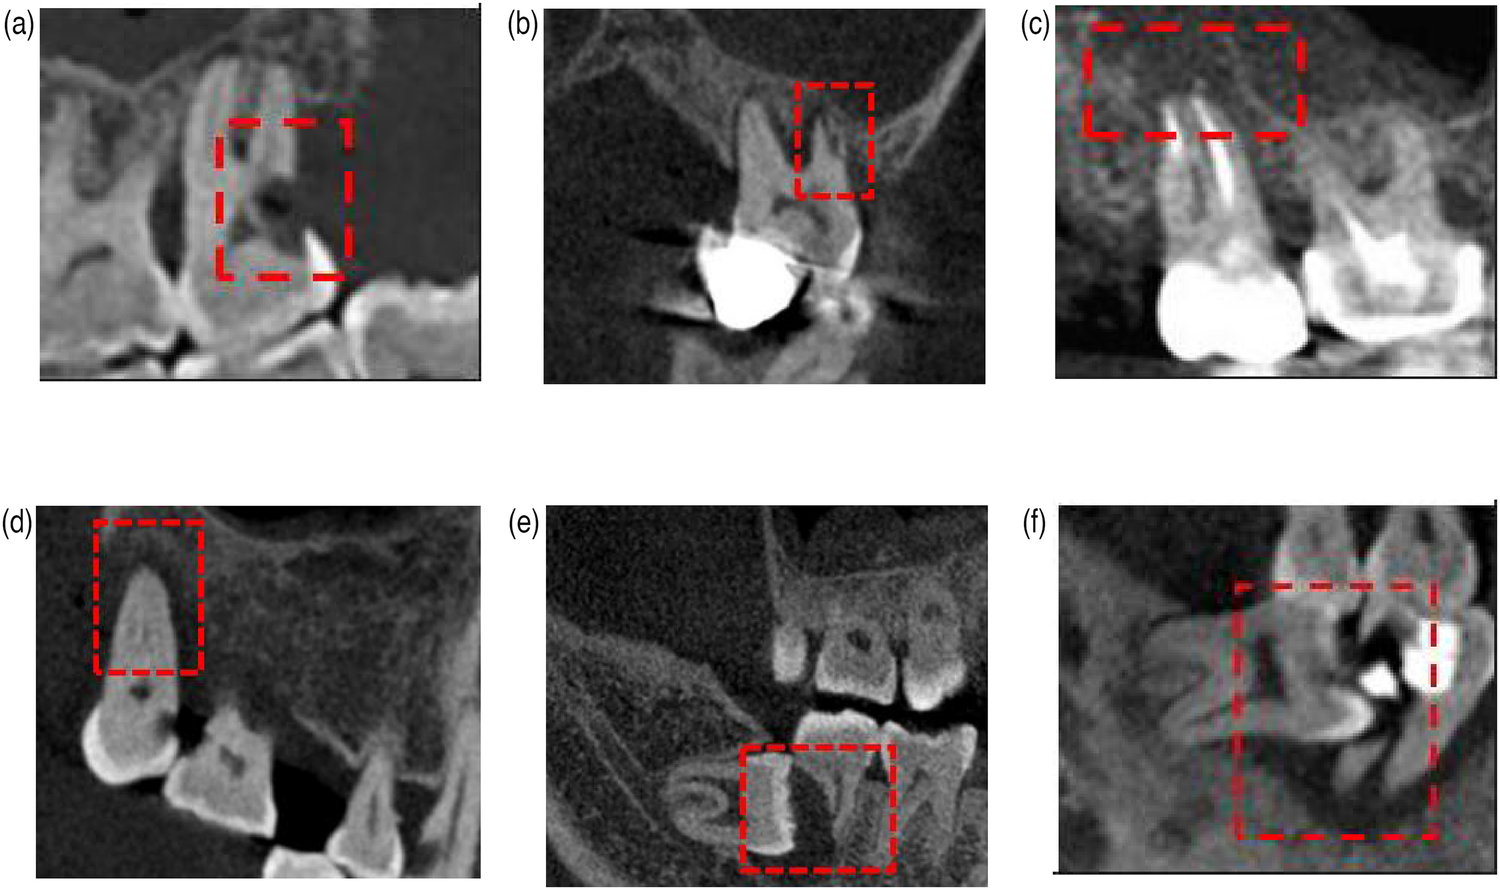

The causes of second molar extraction were categorized into three distinct groups: endodontic factors, periodontal factors, and impacted third molar-related factors (Table 1, Figure 1). Patient demographics and causes were analyzed using SPSS 26.0 (IBM, USA). A significance threshold of P < 0.05 was adopted for statistical inference.

Figure 1

Reasons for second molar extractions. (a) Endodontic factors: severe caries. (b) Endodontic factors: cracked teeth. (c) Endodontic factors: periapical lesions. (d) Periodontal factors: severe periodontitis. (e) Impacted third molar-related factors. (f) Impacted third molar-related factors.